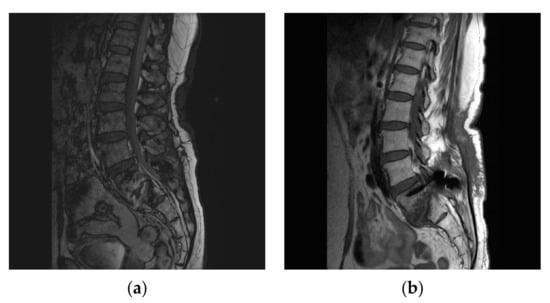

On admission, her vital signs were stable, with a blood pressure of 138/75 mmHg, pulse rate of 75/min, respiration rate of 20/min, and body temperature of 36.7 °C. Blood tests on admission showed an elevated erythrocyte sedimentation rate (ESR) of 73 mm/h and C-reactive protein (CRP) level of 6.0 mg/dL. ESR and CRP are the most common tests to diagnose and monitor inflammatory conditions [6]. MRI showed infectious spondylitis with an abscess at the posteroinferior aspect of the L5 body and epidural enhancement at the L4-S2 level. (Figure 1a)

After a total of 8 weeks’ treatment, follow-up MRI showed no fluid collection, abscess, or epidural enhancement (Figure 1b). Lab tests showed an ESR of 26 mm/h and a CRP concentration of 0.3 mg/dL.

Figure 1. Spine magnetic resonance imaging (MRI) showing infectious spondylitis of L5-S1 with epidural enhancement at the L4-S1 level with decreased disc height and bone marrow signal change before treatment (a) and improvement of fluid collection with no newly developed bony destructive change at and around the L5-S1 level (b).